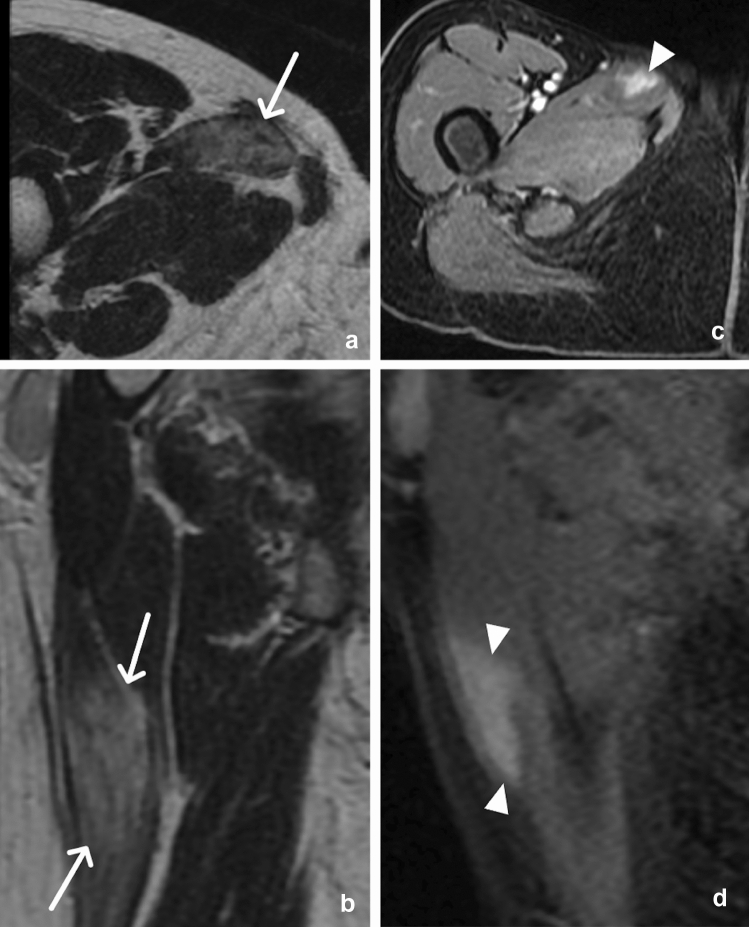

Fig. 1.

43-year-old male with bilateral pectineal muscle myonecrosis. Axial (a) and coronal (b) CT images of the abdomen and pelvis demonstrate ill-defined muscle enlargement and decreased attenuation of bilateral anteromedial compartments of the upper thighs (arrows). Axial (c) and coronal (d) T1W fat-saturated post-contrast MR images demonstrate bilateral peripheral enhancement (arrowheads) of the pectineus muscles surrounding central non-enhancing (arrows) muscle fibers representing myonecrosis

Myonecrosis, also known as muscle infarction, refers to necrosis of muscle fibers. It is most often a complication of late-stage diabetes; however, it is also associated with rhabdomyolysis, severe ischemia, compartment syndrome, crush injury, sickle-cell crisis, and intra-arterial chemotherapy. Often the radiologist will first suspect this condition based on imaging characteristics [8]. The thigh muscles are most commonly affected, and the patient typically presents with pain and low-grade fever without leukocytosis. Imaging may show peripheral enhancement around non-enhancing areas of muscle, representing necrosis on postcontrast images (Figs. 1 and 2). Typically, there is diffuse increased muscular signal, although less than fluid signal, on T2-weighted (T2W) sequences, representing edema [9]. Although not always seen, foci of enhancement within the affected muscle may be present, termed the “stipple sign [9]” (Fig. 3). This should not be confused for intramuscular abscess, especially in the absence of leukocytosis or other infectious symptoms. Although an intramuscular abscess will also show rim enhancement, it should have fluid signal centrally [9] and will be more focal (Fig. 4) as compared to myonecrosis which typically conforms to the shape of the muscle and the abnormality runs parallel to the muscle fibers.